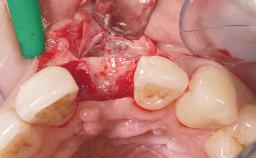

Late Placement of an Implant in a Maxillary Left Central Incisor Site

A 36-year-old female patient was referred for the replacement of the upper left central incisor (tooth 21), which had fractured. Although the tooth had been asymptomatic for many years, the crown began to loosen, at which time she presented to her dentist for an assessment. Teeth 21 and 22 had both been endodontically treated many years previously. She was a healthy individual and a non-smoker.

Bone Augmentation Horizontal|Staged

Augmentation Materials Xenogenous|Membrane

Soft Tissue Grafting Simultaneous

Bone Volume Deficient horizontally, requiring prior grafting